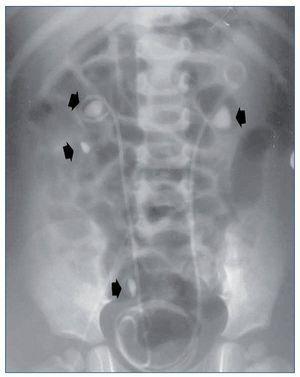

Todos debutaron en la edad pediátrica. La edad promedio al momento del diagnóstico fue de 37,7 meses (2-76 meses) (tabla 1). El seguimiento se extendió hasta 25 años después del diagnóstico en los 2 primeros casos (pacientes 1 y 2). La presentación al debut estuvo relacionada con la presencia de litiasis sintomática (paciente 3), con un hallazgo ocasional (pacientes 1 y 2) o con rechazo de la alimentación e irritabilidad a los 51 días de vida (paciente 4); el hallazgo de leucocituria estéril motivó la solicitud de una ecografía renal, que mostró imágenes de nefrocalcinosis. La paciente 2, poco tiempo después de su diagnóstico, a los 22 meses de vida, sufrió un episodio de fracaso renal agudo anúrico obstructivo secundario a impactación litiásica en ambas uniones pieloureterales en el contexto de una infección por el virus de la varicela. Fue tratada mediante derivación urinaria con catéter doble J bilateralmente (fig. 1) y, después, sometida a litotricia.

Figura 1. Obstrucción bilateral pieloureteral de origen litiásico (flechas), que produjo un cuadro de insuficiencia renal aguda a la paciente 2 cuando contaba 23 meses de edad. Precisó la colocación bilateral de catéter doble J. Obsérvense, además, sendos cálculos en el cáliz inferior y el uréter distal derechos (flechas).